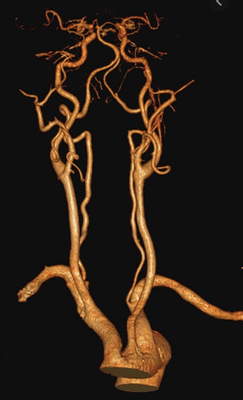

3D-реконструкция артерий шеи при КТА

КТ-ангиография сосудов шеи визуализирует артерии и вены брахиоцефального бассейна. С помощью специальной компьютерной программы, позволяющей придать изображениям объем, рентгенолог видит притоки и мелкие коллатерали, внутренние причины нарушения кровотока, патологические процессы в близлежащих тканях и органах, оказывающие компрессионное действие на артерии и вены. Что показывает КТ сосудов шеи: